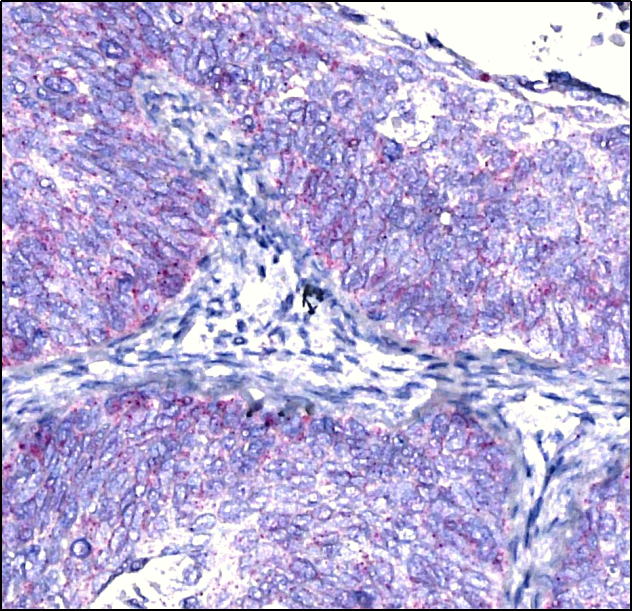

人膀胱癌石蜡切片样品基因原位检测

人乳腺癌石蜡切片样品基因原位检测

人宫颈癌石蜡切片样品基因原位检测